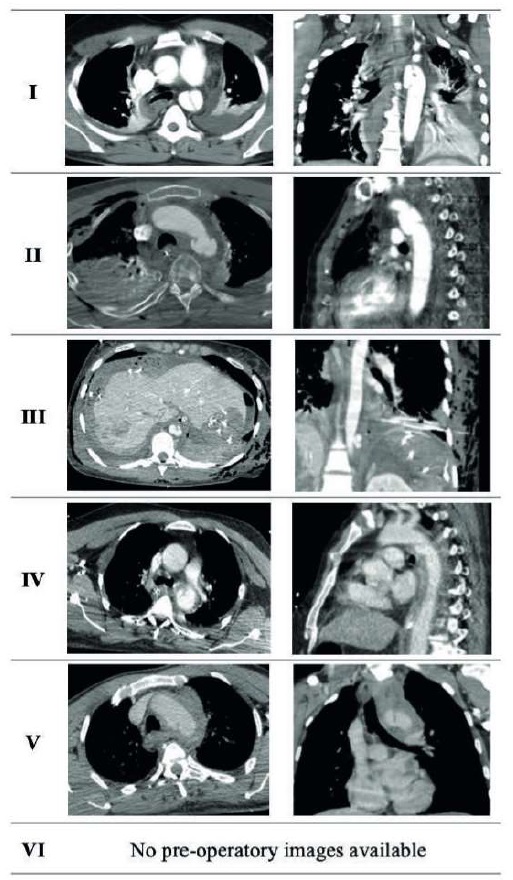

All patients were submitted to CTA at admission (Table 2) which allowed for early diagnosis of TTAI. According to the Classification of TTAI, grade III lesions were present in all six patients. Five patients had pseudoaneurysms at the aortic isthmus, and one patient had a pseudoaneurysm in the transition of the toraco-abdominal aorta. Five patients were submitted to urgent repair with TEVAR, with time from diagnosis to surgery being less than 24 hours. One patient was considered for delayed repair but submitted to surgery for worsening symptoms at 48 hours (progression to hemothorax).